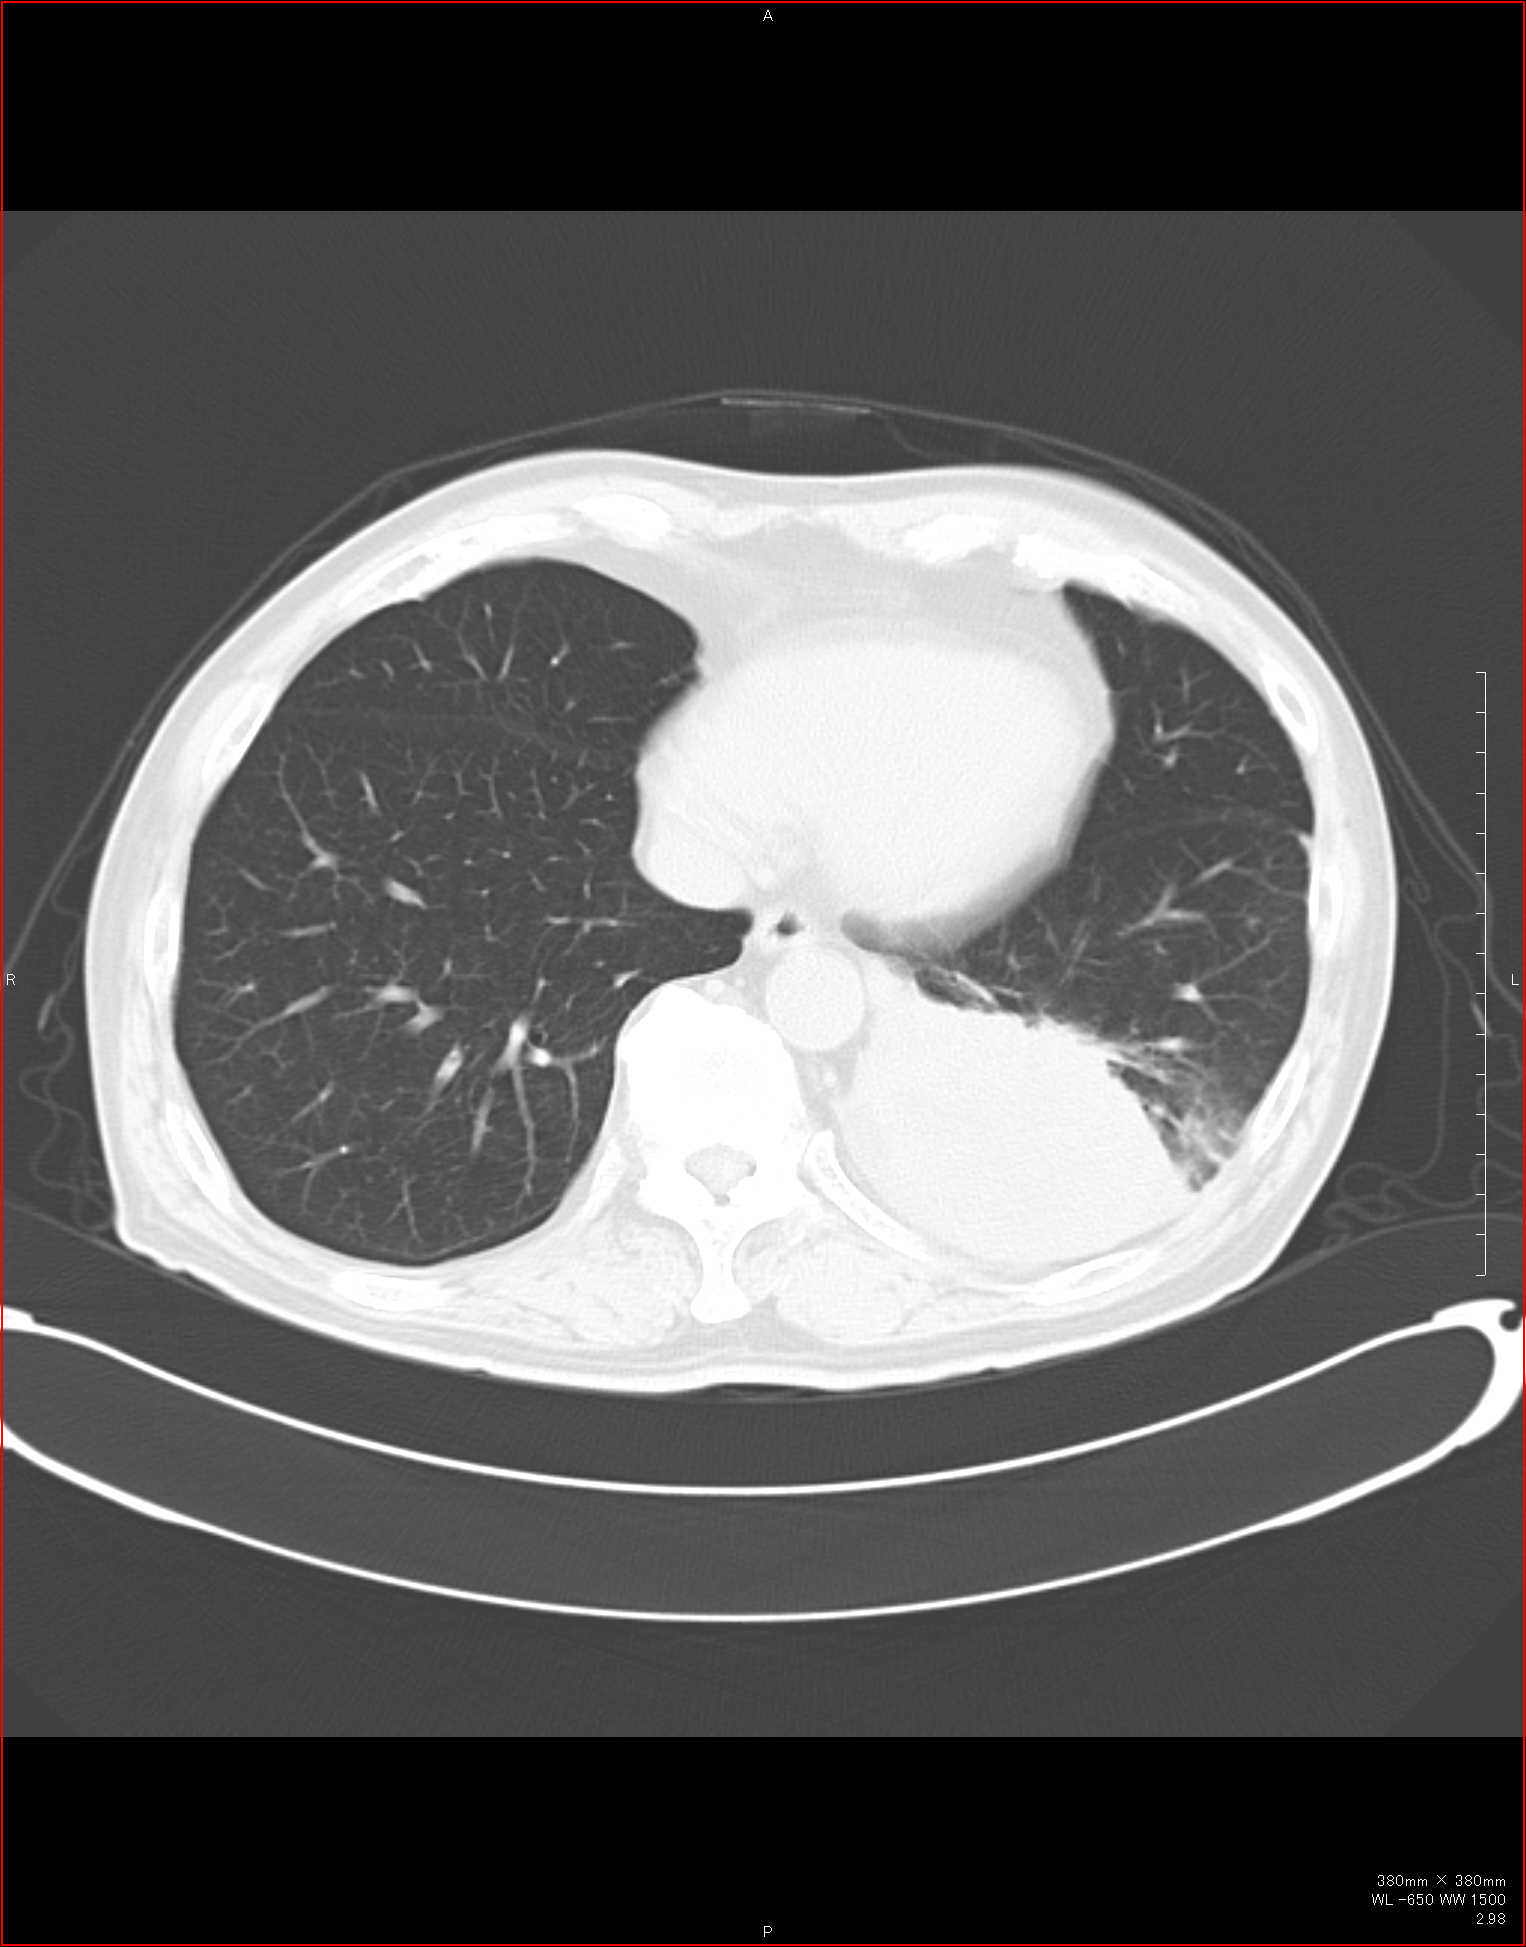

CTで見ると…